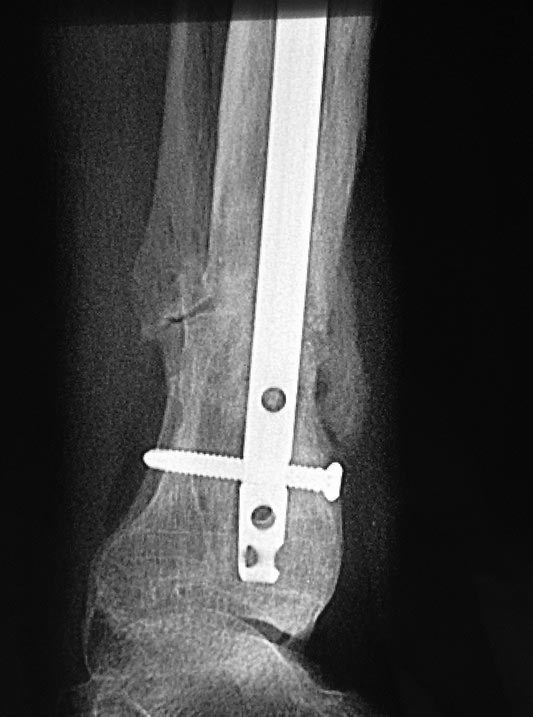

Уважаемые коллеги выразите Ваше мнение по следующему случаю.Молодой человек, 27 лет, находится на лечении с диагнозом: Ложный сустав большеберцовой кости в нижней трети, фиксированный интрамедуллярным блокированным стержнем (12.02.2014 г), ложный сустав малоберцовой кости в нижней трети левой голени, посттравматический артроз левого голеностопного сустава 1 стадии. Укорочение левой нижней конечности на 1,0 см. Со слов пациента известно, что в детстве получил перелом большеберцовой кости, лечился консервативно, перелом сросся с деформацией. Травма в июле 2010 г. бытовая-упал на лестнице, получил перелом малоберцовой кости, и перелом большеберцовой кости без смещения. Выполнена операция: Остеотомия большеберцовой кости в нижней трети, интрамедуллярный блокированный остеосинтез большеберцовой кости левой голени. Гладкое течение послеоперационного периода. Перелом большеберцовой кости сросся. Функция конечности восстановилась. В июне 2013 г выполнена операция удаление интрамедуллярного стержня из большеберцовой кости левой голени. Гладкое течение послеоперационного периода. Приступил к занятием физкультурой, бег. В августе 2013 г спрыгнул с автобуса, с чемоданом в руках, появилась резкая боль в левой голени. За медицинской помощью обратился через 7 дней, при обследовании выявлено: Рефрактура большеберцовой кости. Рекомендовано консервативное лечение в гипсовой повязке. В январе 2014 г. установлен диагноз: Ложный сустав большеберцовой кости в нижней трети, малоберцовой кости в нижней трети левой голени. Контрактура сгибательно - разгибательная левого голеностопного сустава. Посттравматический артроз левого голеностопного сустава 1 стадии. Укорочение левой нижней конечности на 1,0 см. В феврале 2014 г выполнил первым этапом: Фиксацию ложного сустава в АНФ с восстановлением осей сегментов. Через семь дней БИОС с рассверливанием. После операции - вальгус голеностопного сустава. Гладкое течение послеоперационного периода. Нагрузка по переносимости боли. Через 6 недель динамизация, через 2 недели стали мигрировать 2 фронтальных винта. Пытался подкрутить, пришлось удалить. Через 6 мес., контроль - линия ложного сустава прослеживается, но имеется периостальная костная мозоль. Не хватает стабильности.Вопрос что делать?Вариант № 1- выполнить реостеосинтез с рассверливанием КМК и на 12 мм диаметра гвоздь (стоит 11 мм)и убрать ротацию стопы руками одномоментно или одномоментно при помощи АНФ во время операции. Вариант № 2 выполнить удаление гвоздя, сделать все то же, что 6 месяцев назад, но с восстановлением анатомических взаимоотношений в голеностопном суставе.Вариант № 3 Двухэтапно, вторым этапом пластина на большеберцовую кость + костная пластика области не сращения.Вариант № 4 удаление гвоздя и лечение в КДА. Вопросы:1. Какой вариант оперативного лечения будет оптимальным в данном случае.2. При двухэтапной методике в дистальном отломке имеется канал от гвоздя, как направить гвоздь к наружному отделу дистального отломка большеберцовой кости. Есть опасения, что гвоздик может пойти по тому же каналу. Использовать поллер спицы или винты – сработают ли? И достаточна ли будет жесткость фиксации дистального отломка большеберцовой кости на гвоздике при 3 – 4 винтах при реостеосинтезе гвоздем.3. Нужен ли остеосинтез малоберцовой кости в нижней трети, с целью создания латеральной опоры. К сообществу за советом.

Александр Николаевич спасибо за ответ. Три снимка перед внешним видом конечности крайние. На одном из них левая стопа в положении внутренней ротации 15 градусов.

Здесь можно использовать все названные варианты. Гвоздь вполне тоже можно. Надо аппаратом восстановить длину и не повторять прежней ошибки - надо латеральную стенку сопоставить, а не оставлять наружного смещения. Да, надо ввести передне-задние спицы, чтобы не дать стержню попасть в старый канал. И длинной ручной разверткой лучше бы сформировать новый канал.